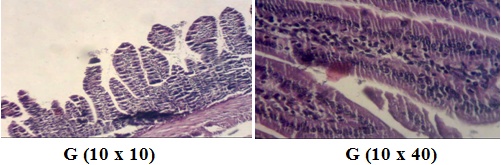

Fig. 6: Microscopic observation G (10 x 40) of intestinal biopsy of mice immunized with α-Lac then fed with coconut milk for 28 d

The villi were increasingly thin and long, bordered by a simple cylindrical epithelium, which was formed with high striated cells corresponding to enterocytes (fig. 6).